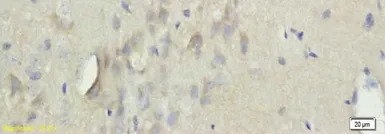

IHC-P analysis of rat brain tissue using GTX37332 TGM3 antibody.